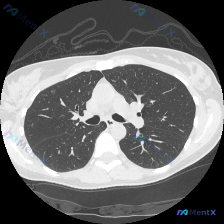

双肺多发微小结节,随机分布——如何一步步排查病因?

整理了一份胸部CT病例,和大家分享分析思路。 病例信息: 胸部CT肺窗横断面(心室水平上方,隆突以下,心脏轮廓可见)显示: - 双肺整体透亮度基本对称,无大片实变、磨玻璃影或空洞 - 气道通畅,无管壁增厚/狭窄 - 胸膜光滑,无胸腔积液/增厚 - 胸廓对称,胸壁软组织无异常 - 异常表现:双肺多处(...